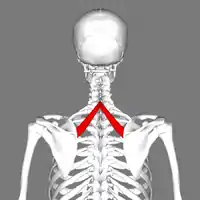

Vue postérieure.

Terminaison

Il se termine sur le bord médial de la scapula au niveau de l'épine scapulaire.

Innervation

Il est innervé par le nerf scapulaire dorsal (C4 et C5)[1].

Fonction et action

Il a comme fonction : fixateur de la scapula contre le thorax et adducteur et élévateur de la scapula.